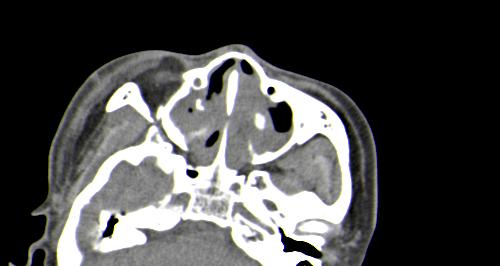

以下是引用皎皎白驹在2006-11-29 8:48:00的发言:[br]影像表现:双侧筛窦和上颌窦、鼻腔内均密度增高,右侧视神经增粗、弯曲,左筛窦顶部筛板及右侧纸板近视神经孔区可见骨折线。[br]结合临床表现考虑:右侧筛窦纸板近视神经孔区骨折致右侧视神经损伤。最好做个眼眶冠状扫描,更明确右侧视神经管是否狭窄。

以下是引用w_jianhua在2006-11-29 10:07:00的发言:[br]影像表现:双侧筛窦和上颌窦、鼻腔内均密度增高,右侧视神经增粗、弯曲,左筛窦顶部筛板及右侧纸板近视神经孔区可见骨折线。[br]结合临床表现考虑:右侧筛窦纸板近视神经孔区骨折致右侧视神经损伤。最好做个眼眶冠状扫描,更明确右侧视神经管是否狭窄。 [br] [br]支持[br]